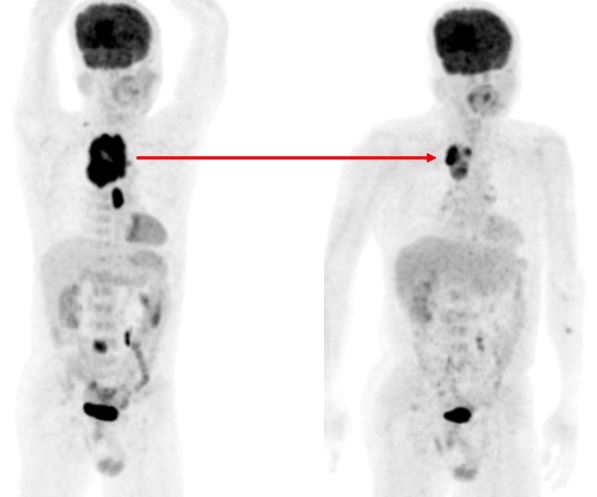

Đáp ứng điều trị: ngay sau chu kỳ hóa chất đầu tiên, bệnh nhân đã cảm thấy dễ thở hơn, không cần hỗ trợ thở oxy. Sau 3 chu kỳ hóa chất bệnh nhân được chụp PET/CT lần thứ hai để đánh giá đáp ứng điều trị.

Trước điều trị: - Khó thở, mất tiếng - CEA=19,78 ng/ml - KT u 5,6x6,5x9,0cm - Max SUV=13,18 - Tổn thương D2 tăng hấp thu FDG | Sau điều trị 3 đợt chu kỳ - Không khó thở, khàn tiếng - CEA=7,96 ng/ml - KT u 3,0x2,5x6,2cm - Max SUV=8,01 - Tổn thương D2 không tăng hấp thu FDG. |

Hình ảnh PET/CT sau khi kết thúc liệu trình điều trị 1 tháng:

Kết quả PET/CT tháng 05/2014: tổn thương thùy trên phổi phải tăng hấp thu FDG nhẹ, theo dõi viêm sau xạ trị.